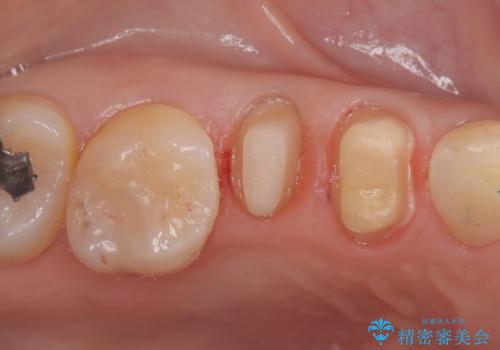

残存歯質を最大限に温存しつつ、フェルールを確保できるよう慎重に形成を行いました。

その後、型取りを行い、精密に適合するセラミッククラウンを作製しました。